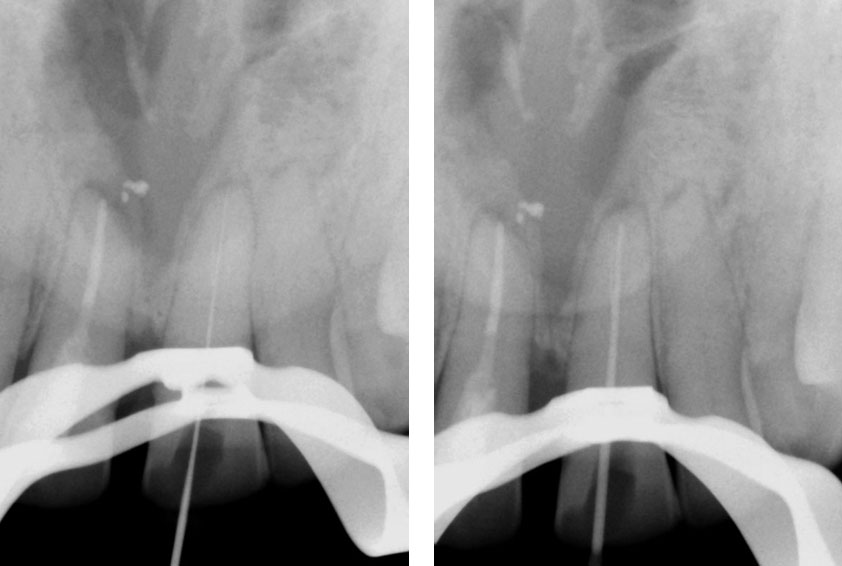

Clinical Case

Broken instrument in the mesio-buccal root of the maxillary second molar.

Pre-op

Residual caries seen after temp removal.

After caries removal

Cotton pellets placed over the palatal and Disto-buccal orifices to prevent the instrument from slipping into those canals.

Fractured instrument in mesio-buccal canal

Fractured instrument removed with ultrasonics

Canals cleaned, shaped and obturated

Fiberglass-post and composite core placed

Post-op

Pre-op & Post-op